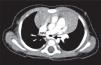

A previously healthy one-month infant was referred to our institution due to a heart murmur. The transthoracic echocardiogram showed the pulmonary trunk giving rise to the right pulmonary artery (RPA), but the left pulmonary artery (LPA) was not identified in its usual location. Instead the LPA was arising from the RPA and coursing leftward behind the trachea, with a turbulent flow (peak velocity 1.5 m/s) (Video 1). An associated ostium secundum atrial septal defect was diagnosed. The suspected diagnosis of pulmonary artery sling was confirmed by computed tomographic angiography. The LPA was seen originating from the posterior aspect of the RPA and coursing over the right mainstem bronchus and then from right to left, posterior to the trachea and anterior to the esophagus, to reach the hilum of the left lung, and causing a mild compression of the origin of the LPA (Figure 1). Besides the pulmonary artery sling and the atrial septal defect, a partial anomalous pulmonary venous return was identified, with the left superior pulmonary vein draining in the left brachiocephalic vein (Figure 2).